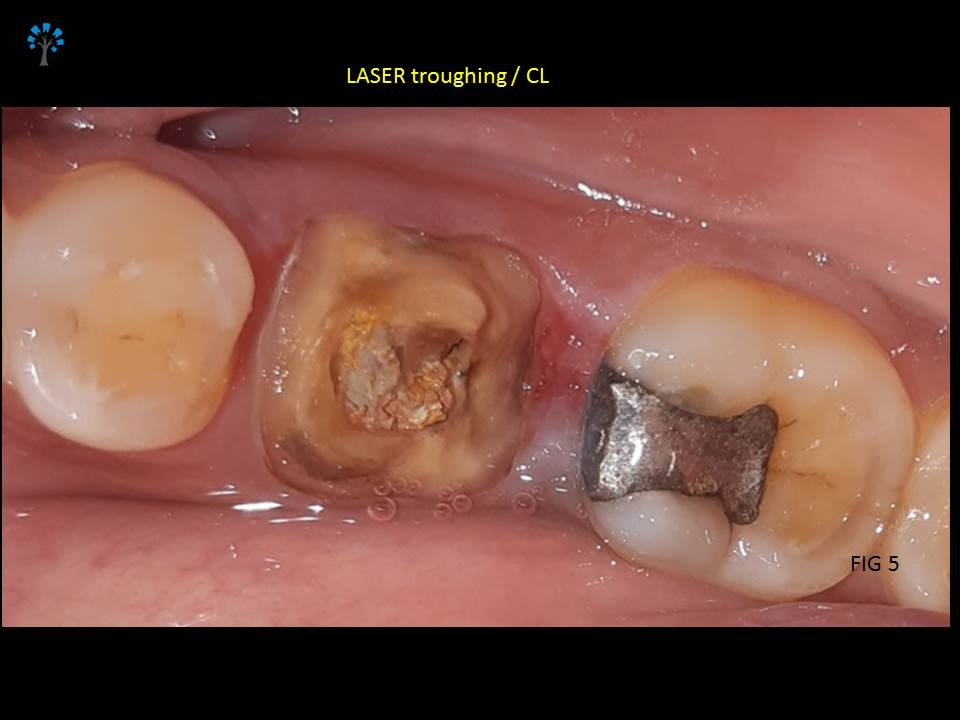

First step was to increase the existing crown length along with some amount of gingivectomy. LASER was employed to do a minimally invasive and Atraumatic procedure. We waited for a few days to allow adequate healing. (Fig 5)